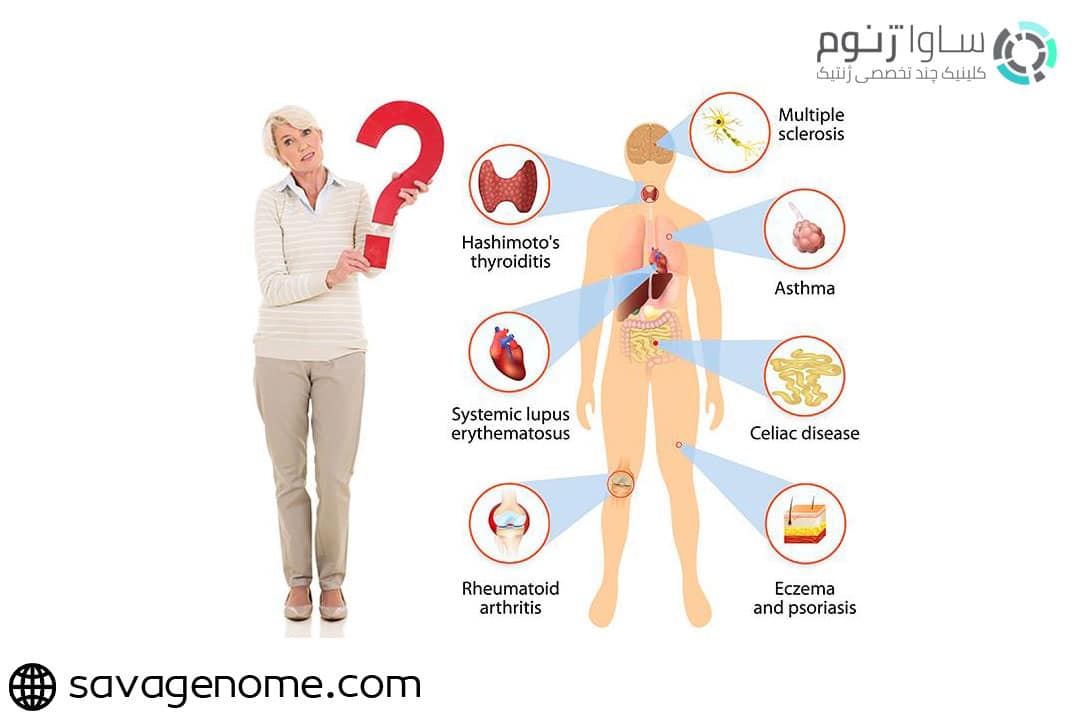

قیمت: 52٬000 تومان - دسته بندی فایل: پاورپوینتپاورپوینت تولرانس ایمنی و خود ایمنی

فروش ویژه ی پاورپوینت حرفه ای تولرانس ایمنی و خود ایمنی با تخفیف استثنایی فقط 71 هزار تومان تعداد اسلایدها: 24 اسلاید